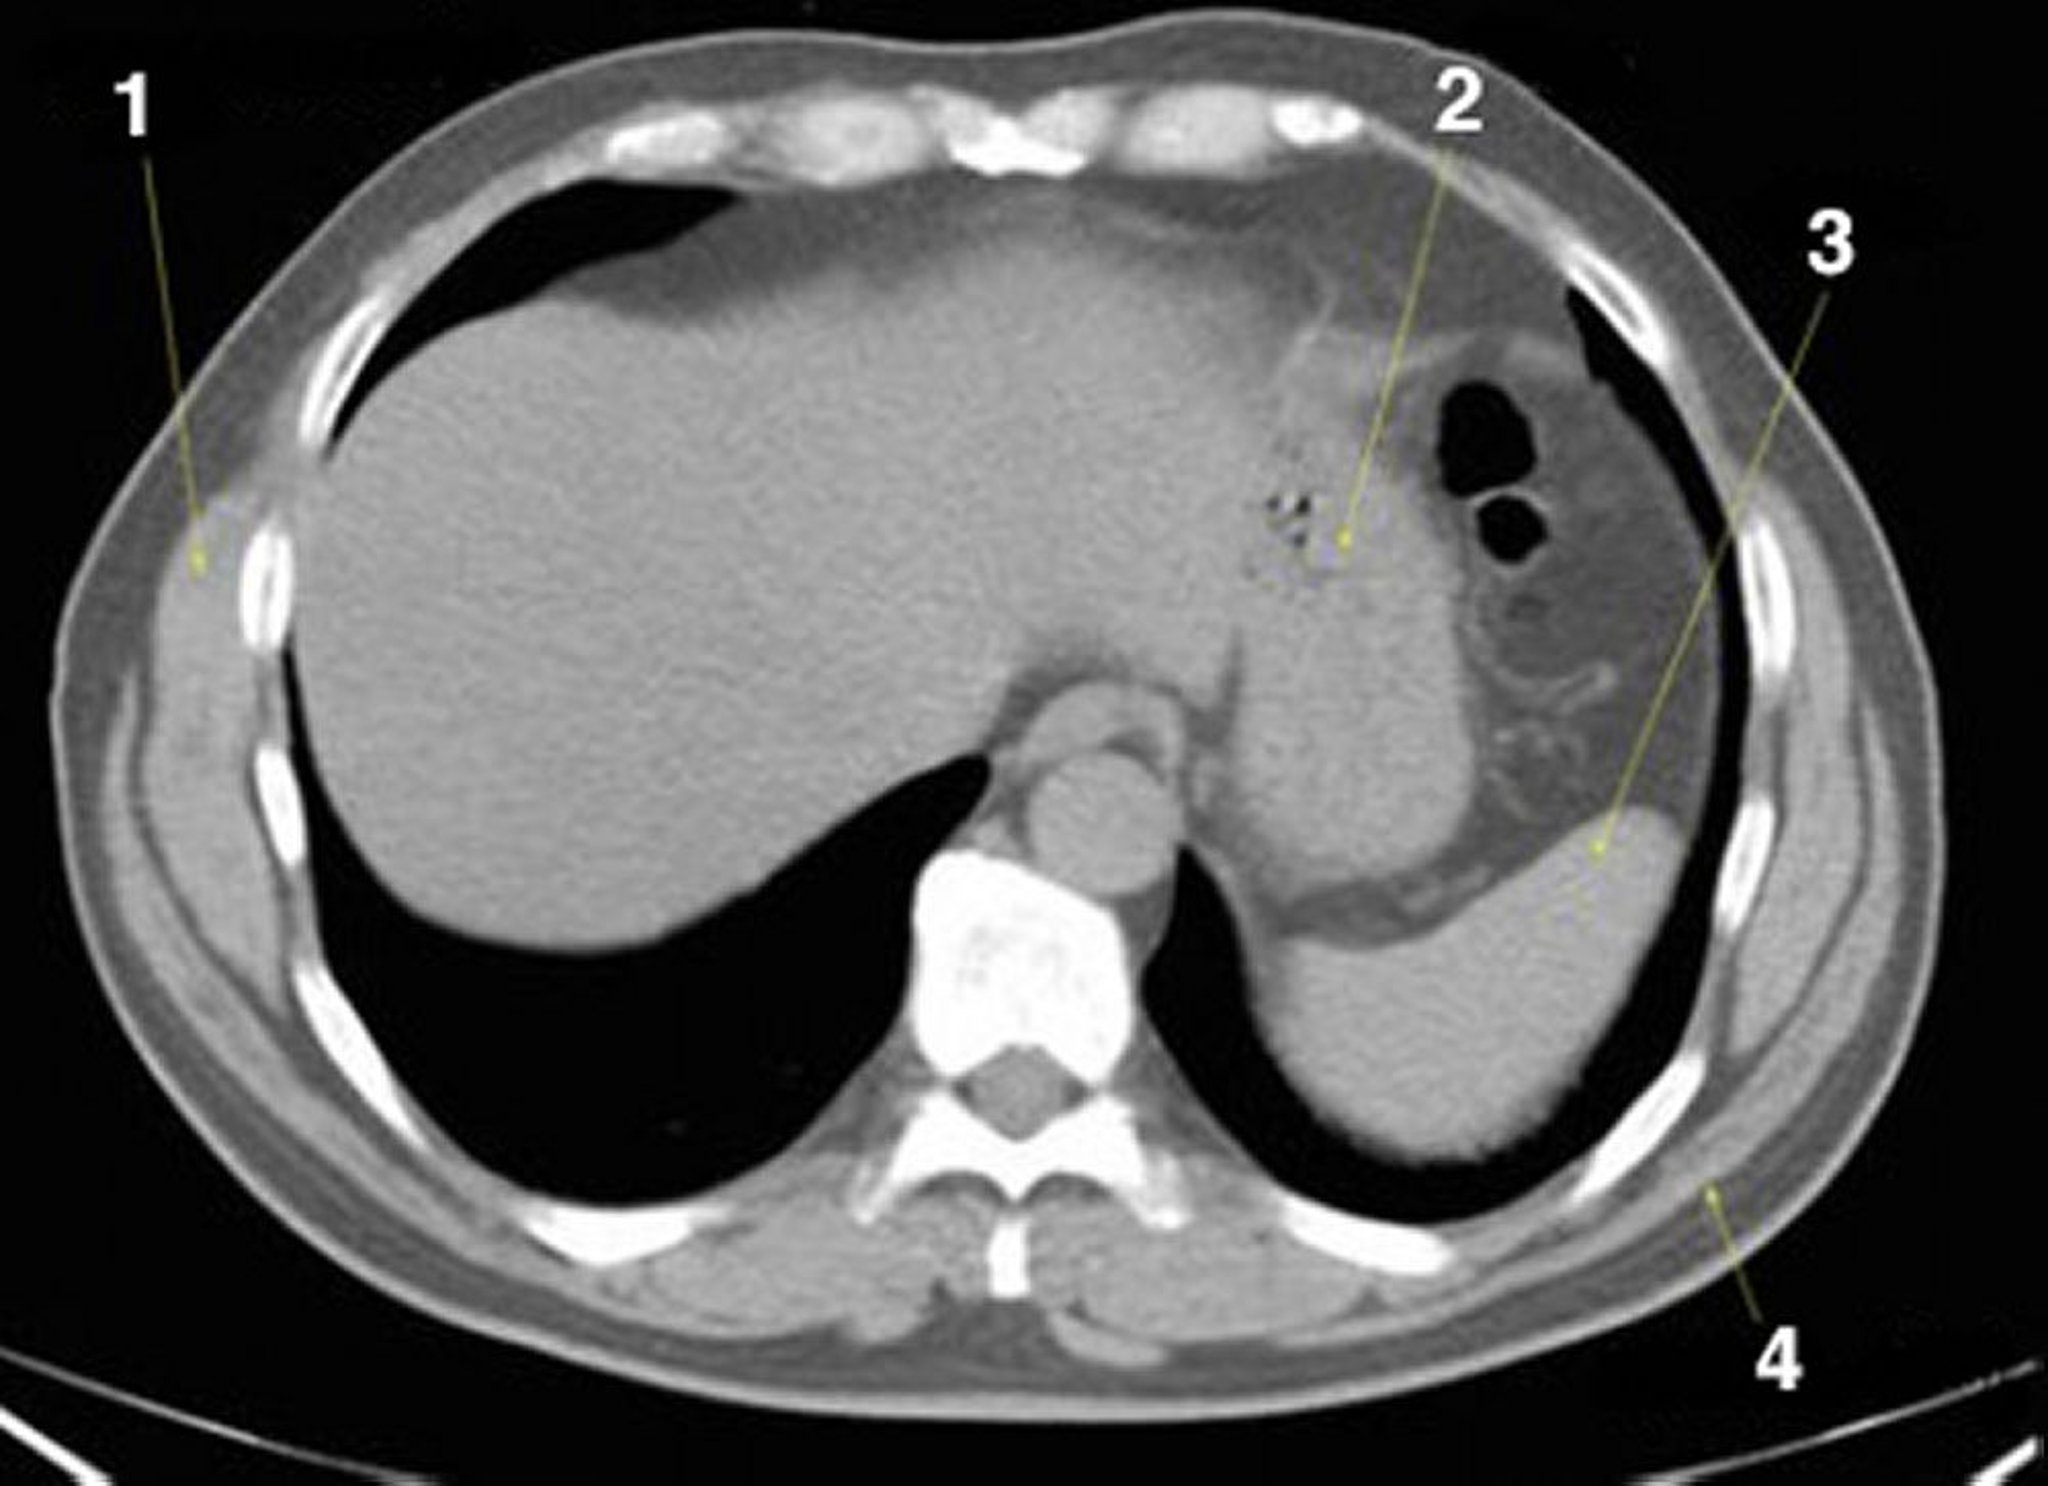

正常解剖を示した腹部および骨盤の単純CT画像(スライド2)

1 = 前鋸筋;2 = 胃;3 = 脾臓;4 = 広背筋。